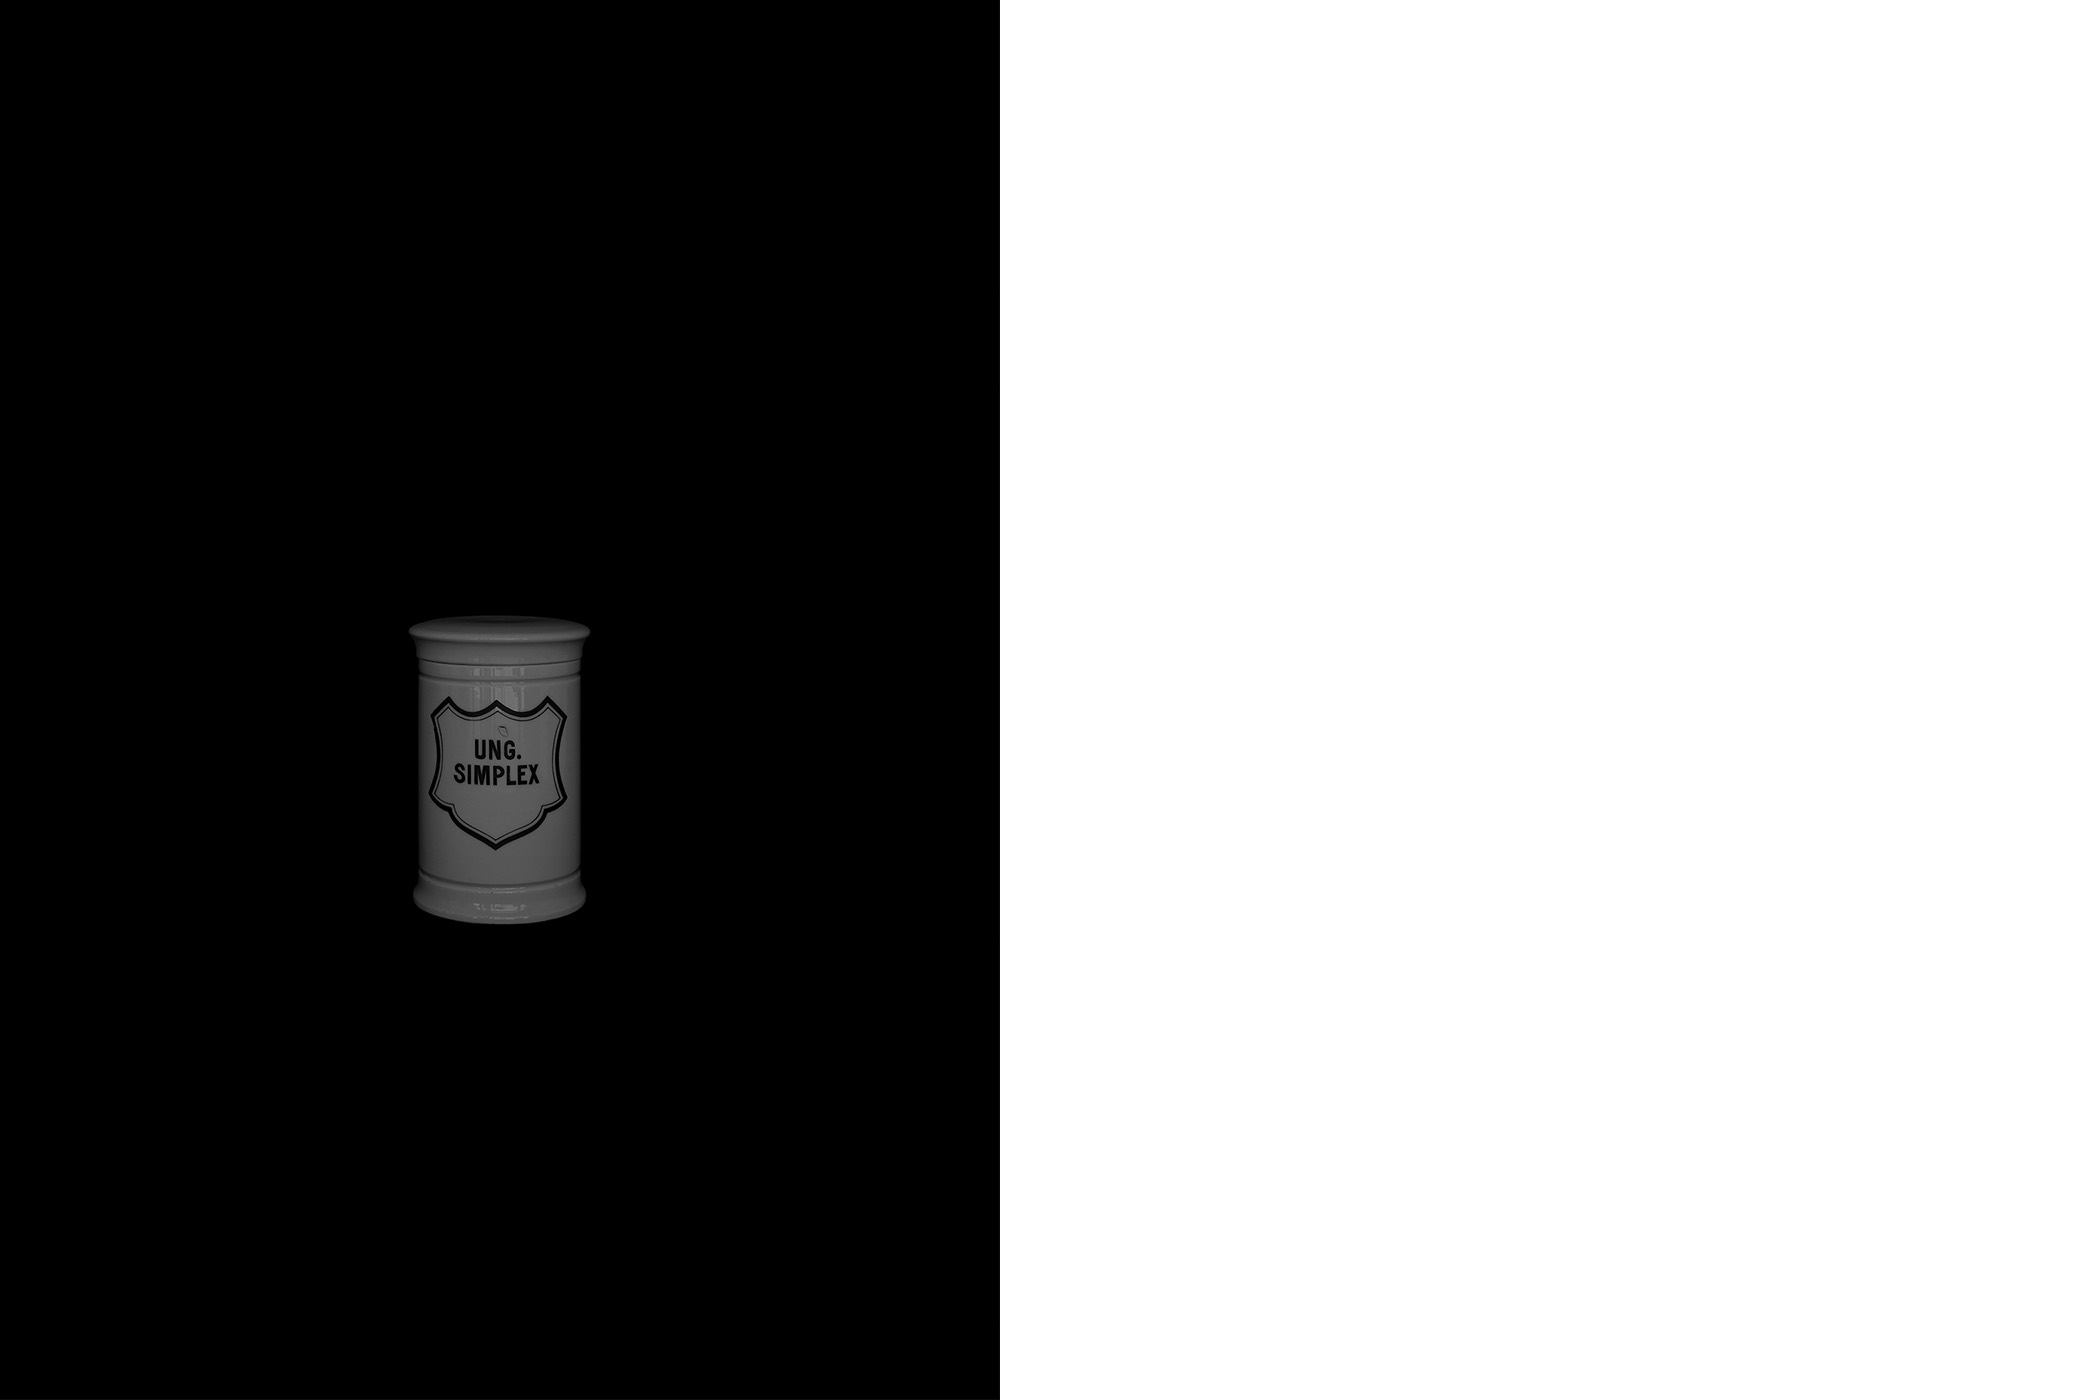

The first series draws from the collection of the Historical and Maritime Museum of Istria, featuring photographs of ceramic and glass apothecary jars transferred onto black paper using silkscreen printing. Instead of traditional ink, the prints were made with powdered active pharmaceutical substances, resulting in faint, almost ghostly images that echo the fragility and ephemerality of the source material.

The first series draws from the collection of the Historical and Maritime Museum of Istria, featuring photographs of ceramic and glass apothecary jars transferred onto black paper using silkscreen printing. Instead of traditional ink, the prints were made with powdered active pharmaceutical substances, resulting in faint, almost ghostly images that echo the fragility and ephemerality of the source material.

Untitled (Archive Pharmacy), 2024

screen printing on paper with color obtained from the powder of the active substances of medicines

graphic sheet 70 x 50 cm, framed 70,5 x 50,5 x 3,5 cm

1-20

Untitled (Archive Pharmacy), 2024

screen printing on paper with color obtained from the powder of the active substances of medicines

graphic sheet 70 x 50 cm, framed 70,5 x 50,5 x 3,5 cm